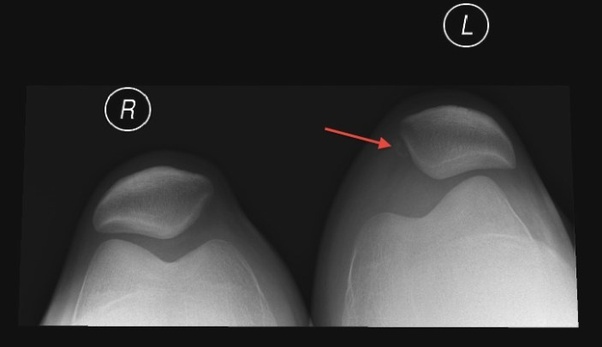

Patellofemoral Joint Replacement Kneecap Replacement Dr. Likover

Image by : www.drlikover.com

Patellofemoral Arthritis OrthoInfo AAOS

Image by : orthoinfo.aaos.org